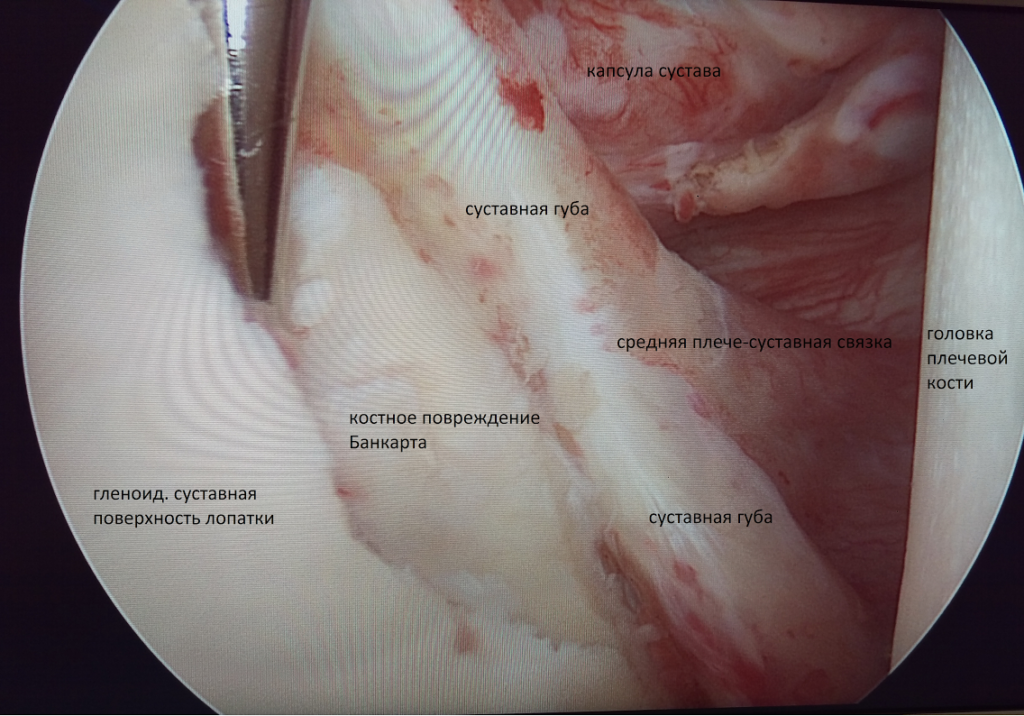

- Нестабильное состояние плечевого сустава (повреждение Банкарта, вывих плеча, в том числе и первичный).

А) При переднем вывихе ПС вмешательство направлено на восстановление суставной губы (операция Банкарта). Метод нацелен на восстановление целостности суставной губы при помощи фиксации оторванной части на край суставного отростка лопатки.

В) В случае сочетания заднего повреждения Банкарта, сопровождающегося задним разрывом связки суставной впадины лопатки, артроскопия позволяет зафиксировать оторванную суставную губу к краю суставной впадины лопатки, заднюю часть капсулы плеча к задней части головки плеча. В качестве фиксатора используются биорассасывающие фиксаторы-якоря. - Эпикондилит. Используется при неэффективности консервативного лечения. Операция сводится к тому, что мышцы отделяют от области прикрепления к мыщелку плечевой кости, затем удаляются хронически воспаленные и измененные ткани. Дальше мышцы обратно прикрепляют к кости.

Головка плечевой кости соответствует по форме суставной впадине лопатки, называемой также гленоидальной впадиной (от латинского термина cavitas glenoidalis – суставная впадина). По краю суставной впадины лопатки имеется суставная губа – хрящевой валик, который удерживает головку плечевой кости в суставе.

Прочная соединительная ткань, образующая капсулу плечевого сустава, по сути, является системой связок плечевого сустава, которая помогает головке плечевой кости оставаться в правильном положении относительно суставной впадины лопатки. Связки прочно срастаются с тонкой капсулой сустава. К ним относятся клювовидно-плечевая и суставно-плечевая связки (имеет три пучка: верхний, средний и нижний). Также плечевой сустав окружен мощными мышцами и сухожилиями, которые активно обеспечивают его стабильность за счет своих усилий. К ним относятся надостная, подостная, малая круглая и подлопаточная мышцы, которые образуют вращательную манжету. Каждая из этих мышц выполняет свою функцию: подлопаточная вращает руку внутрь, надостная — поднимает плечо и «приякоривает» его, т.е. вжимает головку плечевой кости в суставную впадину лопатки при отведении плеча вбок. При этом основная сила отведения определяется дельтовидной мышцей, а надостная мышца работает как командир, направляющий усилия дельтовидной мышцы. Подостная мышца вращает плечо наружу, а малая круглая — тоже вращает наружу и приводит руку к туловищу.